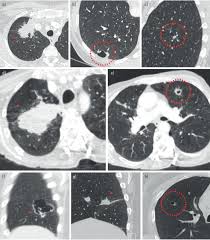

Emphysema is defined as abnormal, permanent enlargement of airspaces distal to the terminal bronchioles and accompanied by the destruction of airspace walls without obvious fibrosis.the main purpose of radiographs in emphysema patients is to exclude comorbidities such as pneumonia, pulmonary oedema, lung cancer, and so on.we are already well informed of the image findings of emphysema and. Can lung cancer be mistaken for copd? That's because the symptoms of emphysema can easily conceal copd, and copd can conceal the presence of lung cancer. Pancreatic cancer may be diagnosed as diabetes, due to the fact that diabetes is often a symptom or risk factor of pancreatic cancer. Malignant tumors trigger inflammation in surrounding normal lung tissue, and they may obstruct your airways and interfere with normal airflow.

Stereotactic Body Radiation Therapy For Early Stage Non Small Cell Lung Cancer A Primer For Radiologists Radiographics from pubs.rsna.org Having copd may put you at risk for lung cancer and heart disease, among other conditions. This is because smoking complications can extend from lung tissue damage (emphysema) to lung cell damage (cancer). When cancer begins in the cells of the lung it is known as primary lung cancer. Various viruses, bacteria, and fungi can cause pneumonia. Lung cancer is a general term that includes all abnormal lung tissue cells that multiply unregulated and form tumors or growths in the lungs.these tumor cells may spread (metastasize) to other parts of the body.; In lung cancer, lung cells exhibit abnormal and uncontrolled growth starting the lungs, while asthma is caused by inflammation and/or mucus that decreases or blocks the breathing passages (bronchioles) of the lungs. Although slipping from emphysema to copd is usually not a drastic decline in health, early detection of lung cancer is critical for increasing your treatment options and improving your prognosis. Initial reports of an association between lung cancer and emphysema date back to the 1950s, when a report on 10 patients with congenital cystic pulmonary emphysema who died from primary lung cancer was published (4).

Tuberculosis Mimicking Lung Cancer Sciencedirect from ars.els-cdn.com This can lead to misdiagnosis as conditions such as irritable bowel syndrome (ibs). This might be the reason your cancer risk goes up with age (the median age for a lung cancer diagnosis is 66). Lung cancer and emphysema are not the same things. Copd is a term used for a group of obstructive lung diseases. While both lung cancer and emphysema can be caused by smoking or exposure to dangerous substances, they cause different problems in the lungs and require different treatments. The relationship between these diseases is instead one based upon mutual risk factors, namely smoking. That's because the symptoms of emphysema can easily conceal copd, and copd can conceal the presence of lung cancer. Pancreatic cancer may also be misdiagnosed as gallstones or pancreatitis, or the inflammation of the pancreas.